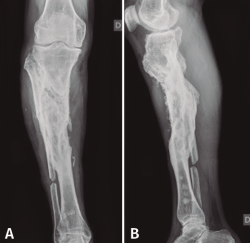

Figura 7. Radiografías de frente y de perfil del extremo proximal de la tibia tras el desbridamiento de la cavidad y el relleno con bolas de cemento con antibiótico.

Con el diagnóstico de osteítis crónica de la tibia se realiza desbridamiento óseo de la cavidad y amplia resección ósea de cortical tibial medial, y relleno de la cavidad con bolas de cemento con antibiótico (Figura 7), con posterior tratamiento antibiótico.

Figura 8. Radiografías del extremo proximal de la tibia donde se objetiva la correcta incorporación del injerto aportado.

Al cabo de 4 meses y tras la resolución del proceso séptico, se procede al relleno de la cavidad con injerto autólogo de cresta iliaca, cuya evolución fue hacia la incorporación de este (Figura 8).